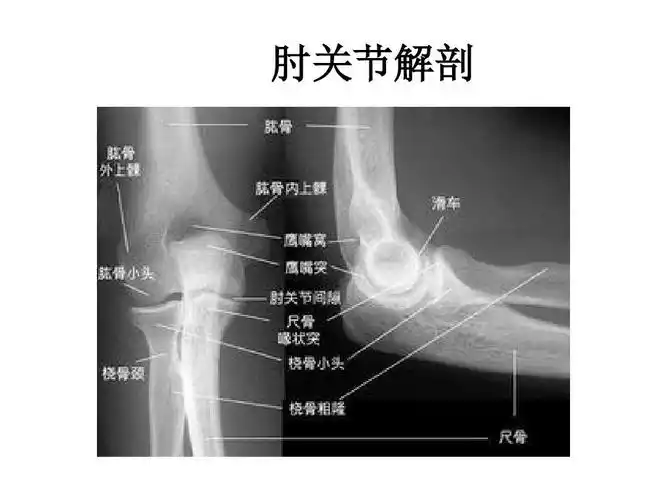

2019--8-26 肘关节x线解剖学